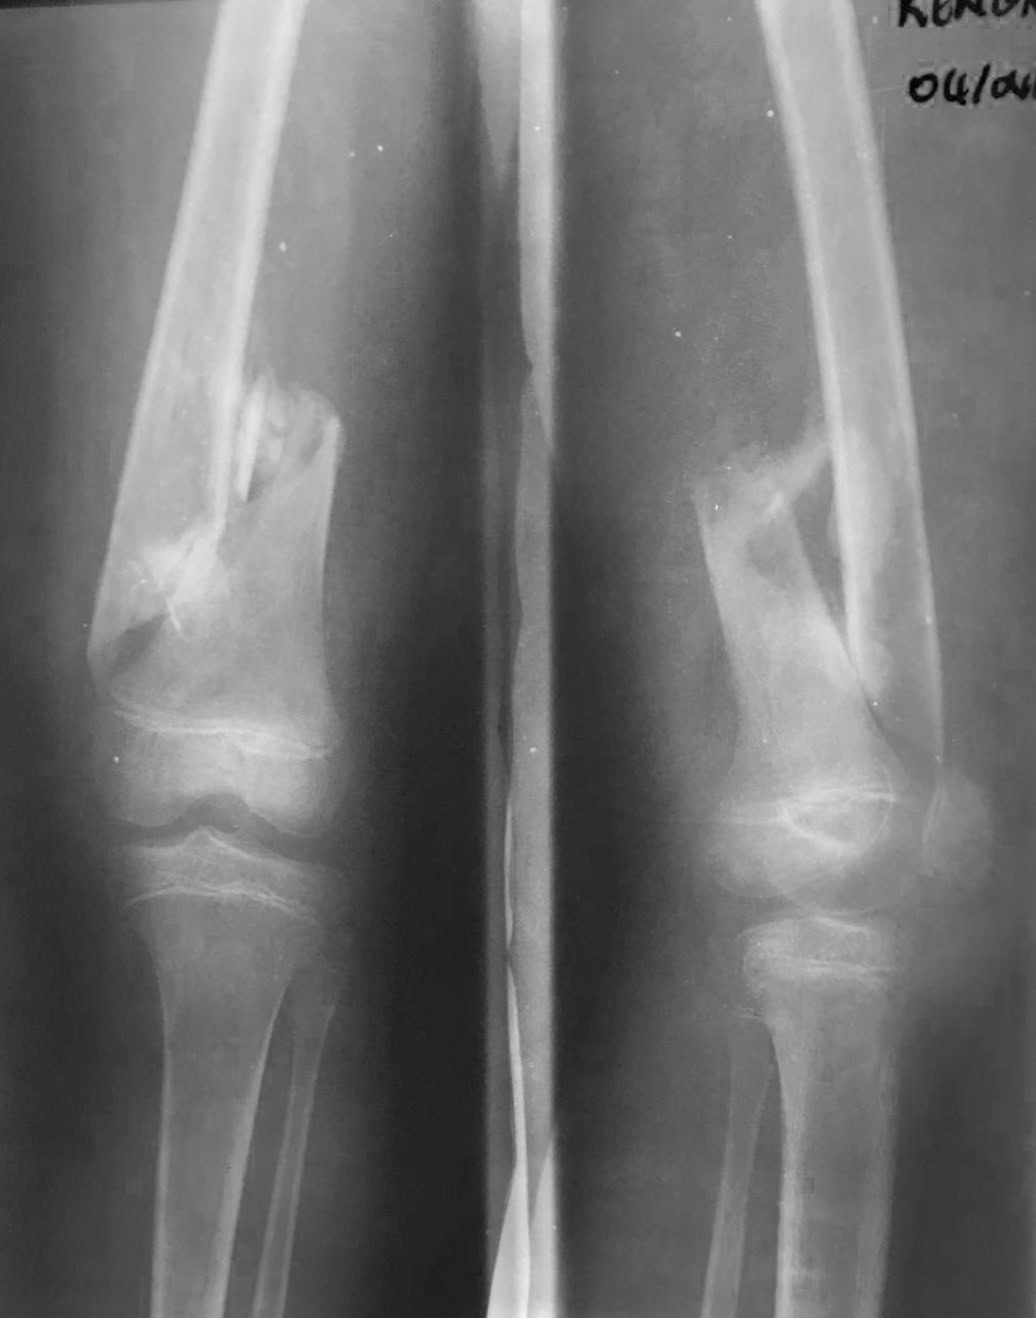

Como no podía ser de otra manera porque nos pasa siempre, nos hemos enfrentado a cirugía de alta complejidad, pseudoartrosis de húmero, fémur y tibia en adultos, así como  fracturas complejas.

Una cosa queda clara, los “masajes tradicionales cameruneses“ no son efectivos en el tratamiento de las fracturas de cualquier hueso, tanto en niños como en adultos y conducen inevitablemente a pseudoartrosis  muy difíciles de tratar.

Y como traca final, el viernes por la tarde cuando íbamos a preparar ya las maletas para el viaje de vuelta, tuvimos  dos urgencias que requerían cirugía  de urgencia. Una artritis séptica de rodilla en un paciente de 21 años operado en otro centro hacía tiempo de un Girldestone por lo que suponemos fueron las complicaciones de una artritis séptica de cadera y con una osteomielitis del fémur. Y un paciente con luxación abierta de rodilla, fractura de cóndilo externo y fracturas abiertas de metatarsianos. Osea, toda la tarde del viernes trabajando.